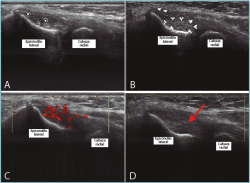

Hay estudios que demuestran que los síntomas y cambios estructurales degenerativos en la epicondilitis lateral crónica se reducen después del tratamiento con corriente galvánica intratisular bajo control ecográfico, asociado a ejercicios excéntricos y de estiramiento(22,23)(Figura 4).

Figura 4. Imágenes ecográficas del compartimento lateral del codo. A: imagen ecográfica en eje longitudinal del epicóndilo lateral y la inserción tendinosa del extensor carpis radialis brevis (ECRB), en la que se objetiva una lesión intratendinosa y calcificaciones intratendinosas; B: delimitación ecográfica de la lesión con flechas; C: la eco-Doppler muestra el aumento de vascularización en la zona de degeneración tendinosa; D: los cambios estructurales que se consiguen tras el tratamiento con corrientes galvánicas intratisulares.